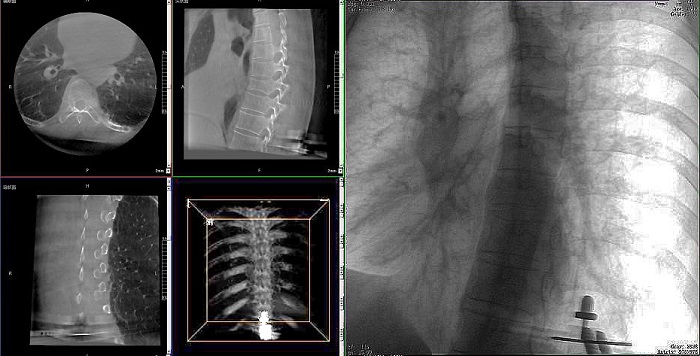

①機器人輔助胸椎手術操作難點之圖像采集

胸椎緊鄰肺部,患者的呼吸運動會造成椎節的相對移動,獲取清晰、穩定的影像較為困難。高質量的影像是精準導航的重要前提,胸椎手術中,如果呼吸造成的移動無法得到有效控制,則會降低導航的精度,增加手術風險。人體深吸氣胸圍與深呼氣胸圍的差值約為6~8厘米。

普愛醫療手術導航定位系統解決方案

高清三維成像:普愛醫療精研三維成像技術13年,自研的三維C形臂可為手術提供清晰、穩定的三維圖像,為醫生精準開展胸椎手術提供影像保障。

亞毫米級精度:普愛醫療三維C形臂+骨科手術機器人,基于同一技術平臺研發,借助一體化自適應配準及無損圖像傳輸技術,整體協同性更高,精度可達亞毫米級。

快速掃描:麻醉師通過適當的呼吸控制,配合三維C形臂的快速掃描模式,可以在短時間內完成圖像采集,減少因呼吸運動造成的圖像干擾。